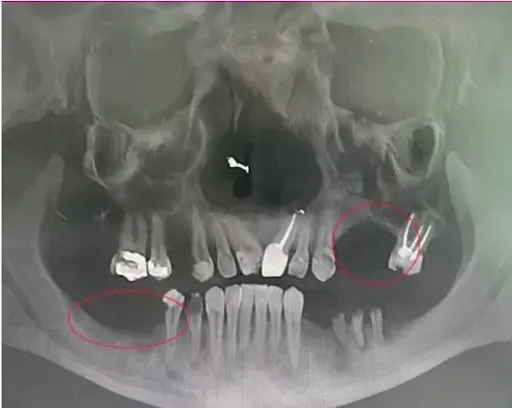

Here's what most people don't understand: Every day you wait, you lose more bone.

Infection causes bone to deteriorate and soften—like a piece of untreated wood left in the rain. Eventually, it becomes too soft to support implants.

The scan above shows severe infection (dark holes where bone should be). This person waited too long and is no longer a candidate for dental implants—confined to dentures forever.